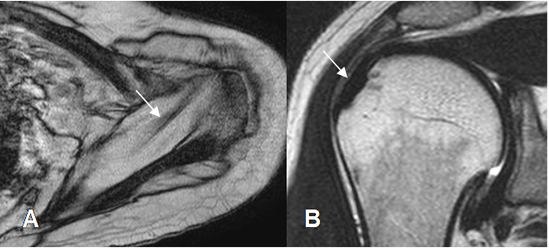

Los tendones de todos los grupos musculares, se aprecian como estructuras hipointensas en todas las secuencias, en relación con los sitios de origen e inserción. (Fig 12 a 17).

Fig 12. Tendón del supraespinoso normal.

A: RM axial en FFE y B: RM coronal en T2. Supraespinoso normal, con inserción en la tuberosidad mayor.

Fig 13. Tendón del infraespinoso normal.

A: RM axial en FFE y B: RM coronal en T1.